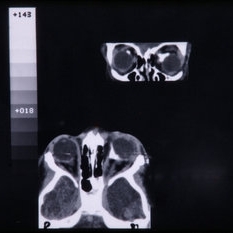

CT Scan of Brain Showing Cerebral Hypoplasia

CT Scan of Brain Showing Cerebral Hypoplasia

Feb 20 2015 by H. Michael Lambert, MD

CT scan of brain showing cerebral hypoplasia

Condition/keywords: cerebral hypoplasia, CT scan, linear nevus sebaceous syndrome